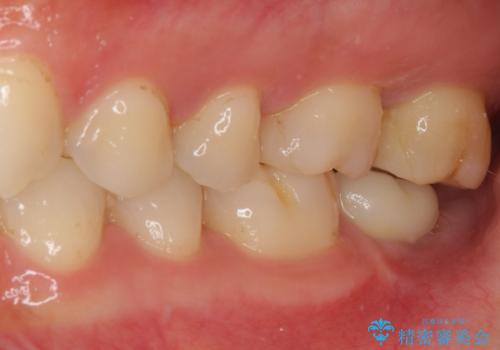

強い咬合力を負担する第一大臼歯であるため、根管治療後は速やかにオールセラミッククラウンにて補綴治療を行うこととしました。